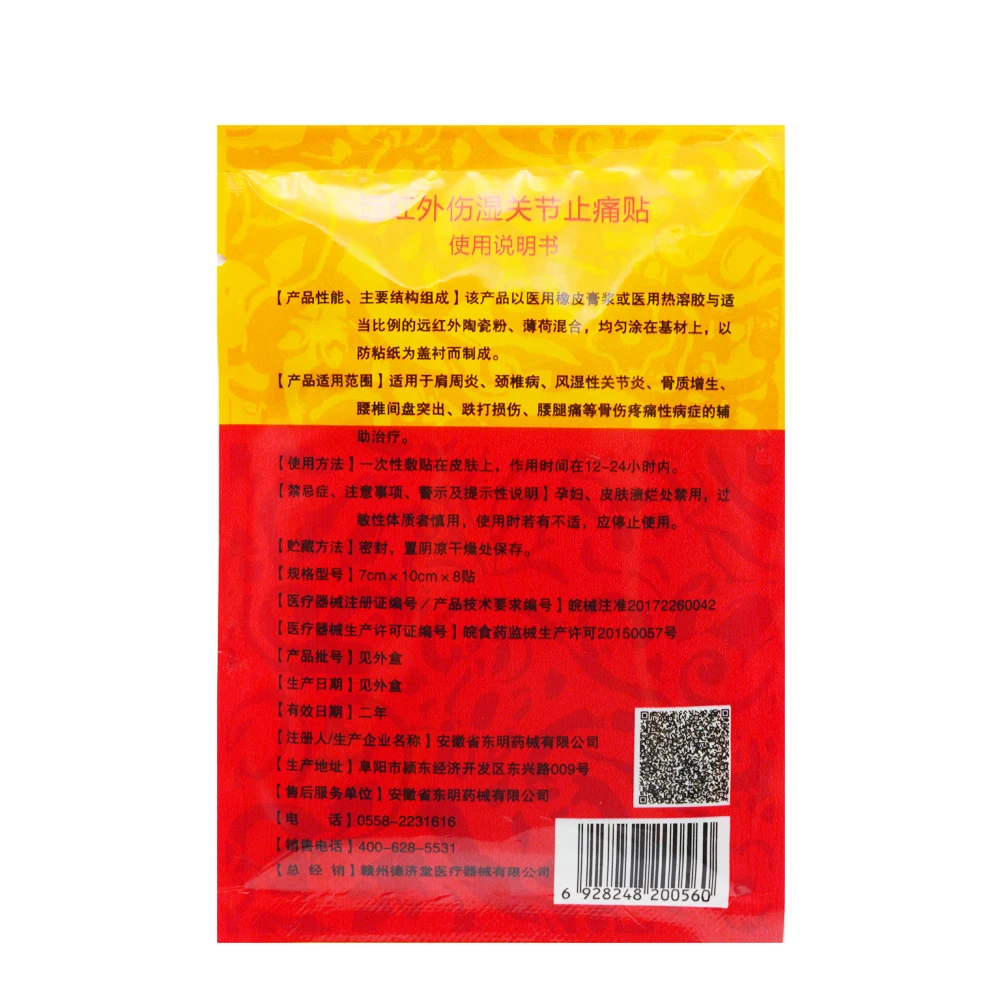

Medical Muscle Pain Patch, Arthritis, Osteochondrosis, Joint Pain, Bruises, Pain Relief Plaster Medical Patch 8pcs

Scope of application: for pain caused by cervical pain, frozen shoulder, lumbar pain, knee joint and soft tissue injury. Precautions: The following conditions are disabled. Those who are allergic to this product, Skin ulcer, and wound, pregnant women, infant. ·Chinese Pain Relief Plaster is a flexible pain relieving...

Scope of application:

for pain caused by cervical pain, frozen shoulder, lumbar pain, knee joint and soft tissue injury.

Precautions:

The following conditions are disabled. Those who are allergic to this product, Skin ulcer, and wound, pregnant women, infant.

·Chinese Pain Relief Plaster is a flexible pain relieving patch.

Structure and Material:

Consist of far IR ceramic powder,medical PSA,non-woven,release paper etc.

Structure and Material:

Consist of far IR ceramic powder,medical PSA,non-woven,release paper etc.